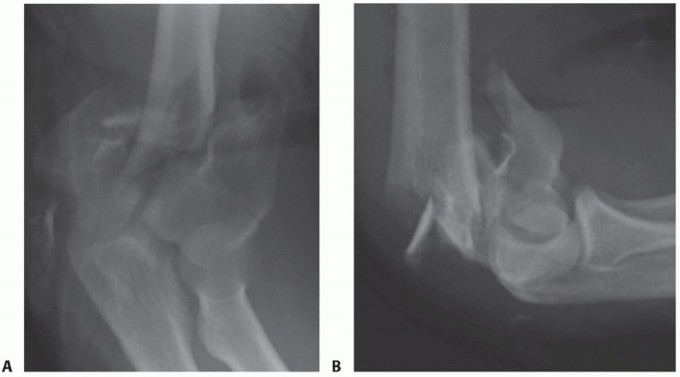

Plain radiographs, including anteroposterior (AP) and lateral views (FIG 2) of the elbow and both wrists,

should be obtained. The elbow view may have to be taken in a protective splint or plaster backslab for patient comfort.

Elbow radiographs will allow initial assessment of the degree of comminution and may indicate the presence of decreased bone mineral density.

FIG 2 • Standard AP (A) and lateral (B) plain radiographs.*